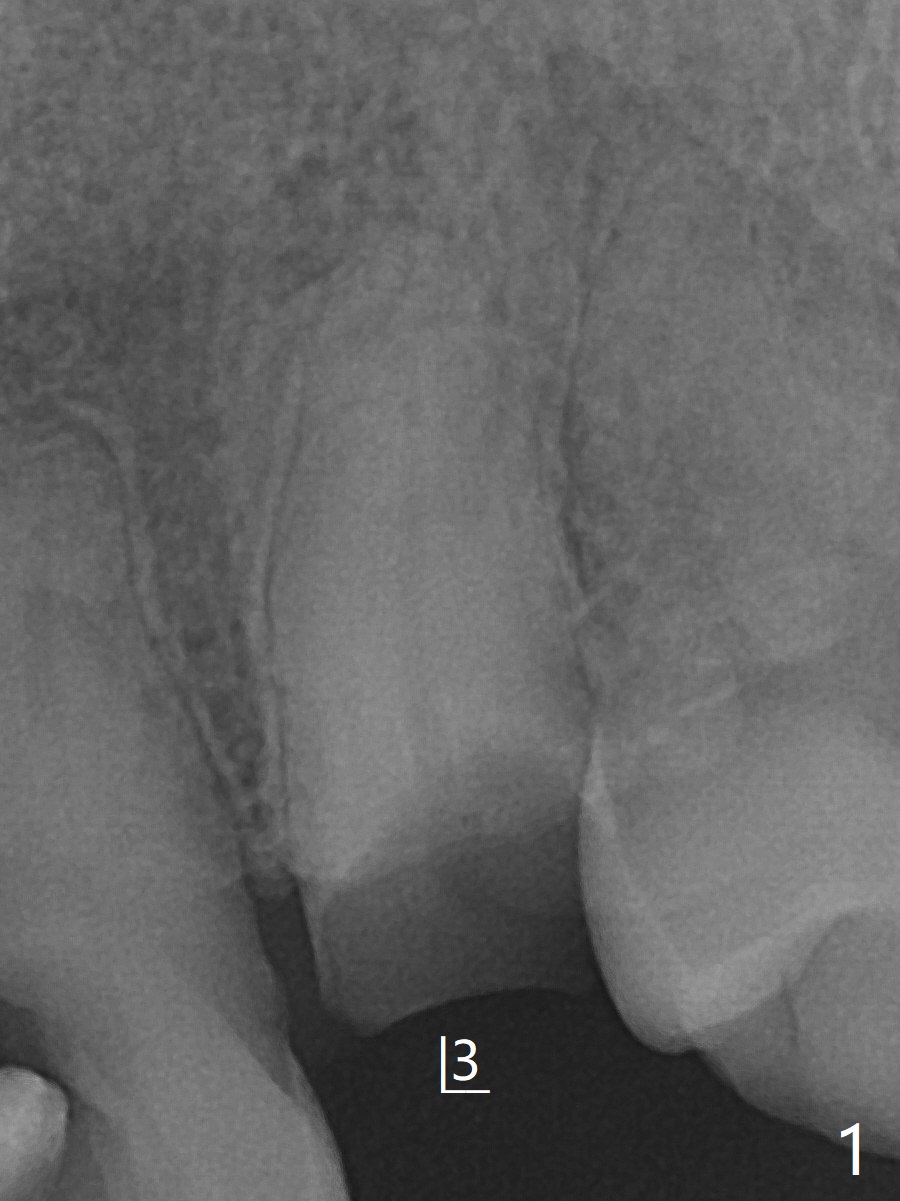

64岁男要求拔除左上3(图一,二),将使用Piezo P3 tip(图三)松动牙根,可行?其实图三是G6,used for removal of calculus from a wide plane. G:可能代表general use or general dentistry,而P牙周(图四)。P3(买了好久,不知道用处)特别细长,容易进入牙周膜,但愿在小功率的普通Piezo Scaler (超声洁牙机)作用下,P3能切断牙周膜,午饭后尝试。其实尖牙无症状(图五),中切牙(在侧切牙位置上)因近中深龋造成牙龈炎症,在病人要求下,清除龋坏后,填入临时充填物(图五,六)。